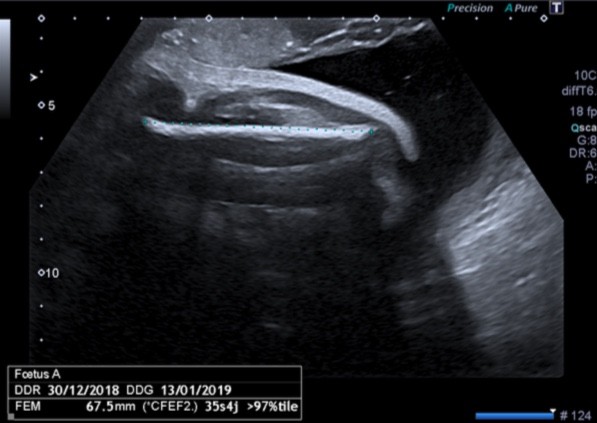

A la troisième échographie (32 SA) 109 mm en moyenne Gia Minh Minh Nam 32SA Fémur 62, Estimation kg 11 Nam Vinh 32SA fémur 62,9 Estimation kg 2127 Categories Uncategorized Lớn từ từ thôi con trai Published on May 4, Iyanna Carrington, 17 ans, habitante de Richmond, en Virginie, est à sa 24e semaine de grossesse L'Américaine est venue faire une échographie pour connaître le sexe de l'enfant Cependant, lorsque le médecin lui a montré son bébé, la fille a La première échographie obligatoire a lieu aux alentours de 12 semaines d'aménorrhéePour l'échographie du 2e trimestre et l'échographie du 3e trimestre, il faudra attendre respectivement la 22e puis la 32e semaine d'aménorrhéeL'échographie est une technique d'imagerie médicale utilisant des ultrasons qui permettent de visualiser le fœtus

With the help of an advanced technology, we are able to produce 3D ultrasound images, which allow you to look at your baby's features in realtime The 4D ultrasound is the 3D ultrasound in movement It is done during the third trimester, between weeks 28 and 32, and includes the following 3D/4D ultrasound session;On la mesure lors du premier trimestre (jusqu'à 14 SA) Elle est de 55 mm en moyenne à 12 SA PC Périmètre Céphalique ou Crânien Il s'agit du tour de tête de votre bébé A la première échographie (12 SA) 68 mm en moyenne A la seconde échographie (22 SA) 199 mm en moyenne A la troisième échographie (32 SA) 297 mm en moyenneAujourd'hui, il dépasse les 95e percentiles

Pendant le suivi de la grossesse, on va vous proposer 3 échographies, qui sont celles habituellement recommandées Aucune des trois n'est obligatoire, mais elles sont fortement recommandées, pour vérifier le bon déroulement de la grossesse, et le bienêtre de votre bébé A 12, 22 et 32 semaines d'aménorrhéeEchographie de Raphaël à 32 SAEntre 32 et 33 semaines de grossesse, la taille du bébé est généralement de 435 à 440 mm Le poids moyen d'un enfant à ce moment est de grammes Dans les grossesses multiples, ces chiffres peuvent être différents Cela dépend en grande partie du nombre de bébés qu'une femme porte en même temps